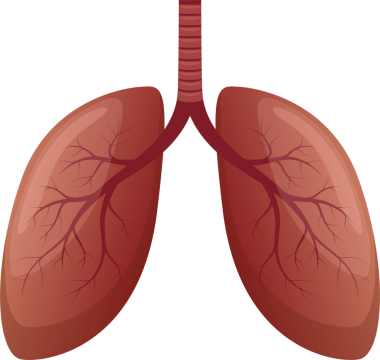

Sağlıklı Bir İnsan Akciğerinin Anatomisi, El Çizimi Suluboya Çizimi

Nefes alsuluboyaOksijenuçak yolculuğuHavalandırmaApexsolunumnefes borusubronşalveollersolunum yolukarbon dioksitSolunum SistemiAnatomik yapısıinsan akciğerMedikal illüstrasyonbronchiolesakciğer fonksiyonbasit örnekthoracic cavityrespiratory healthGaz değişimiVital kapasitehealthy lungmiddle lobetidal volumenormal lungüst lobalt lobbiyolojik diyagramBenzer İçerikler